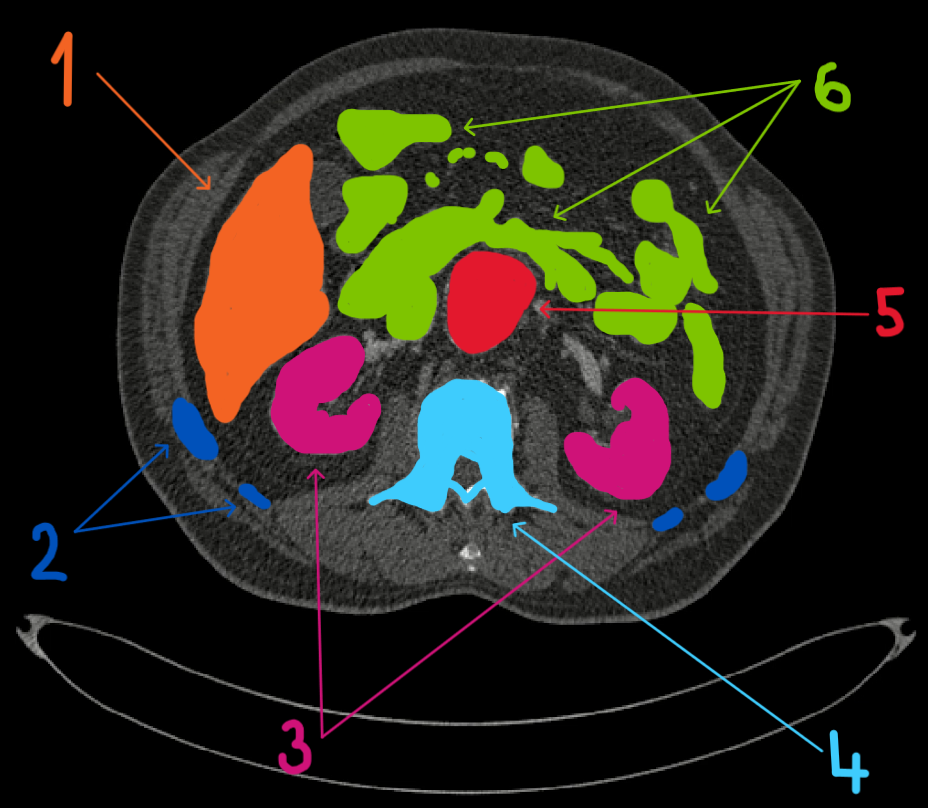

Horní oblast dutiny břišní (z videa)

- játra

- hrudník (žebra)

- ledviny

- obratel páteře

- aorta břišní (s aneurysmatem)

- střeva